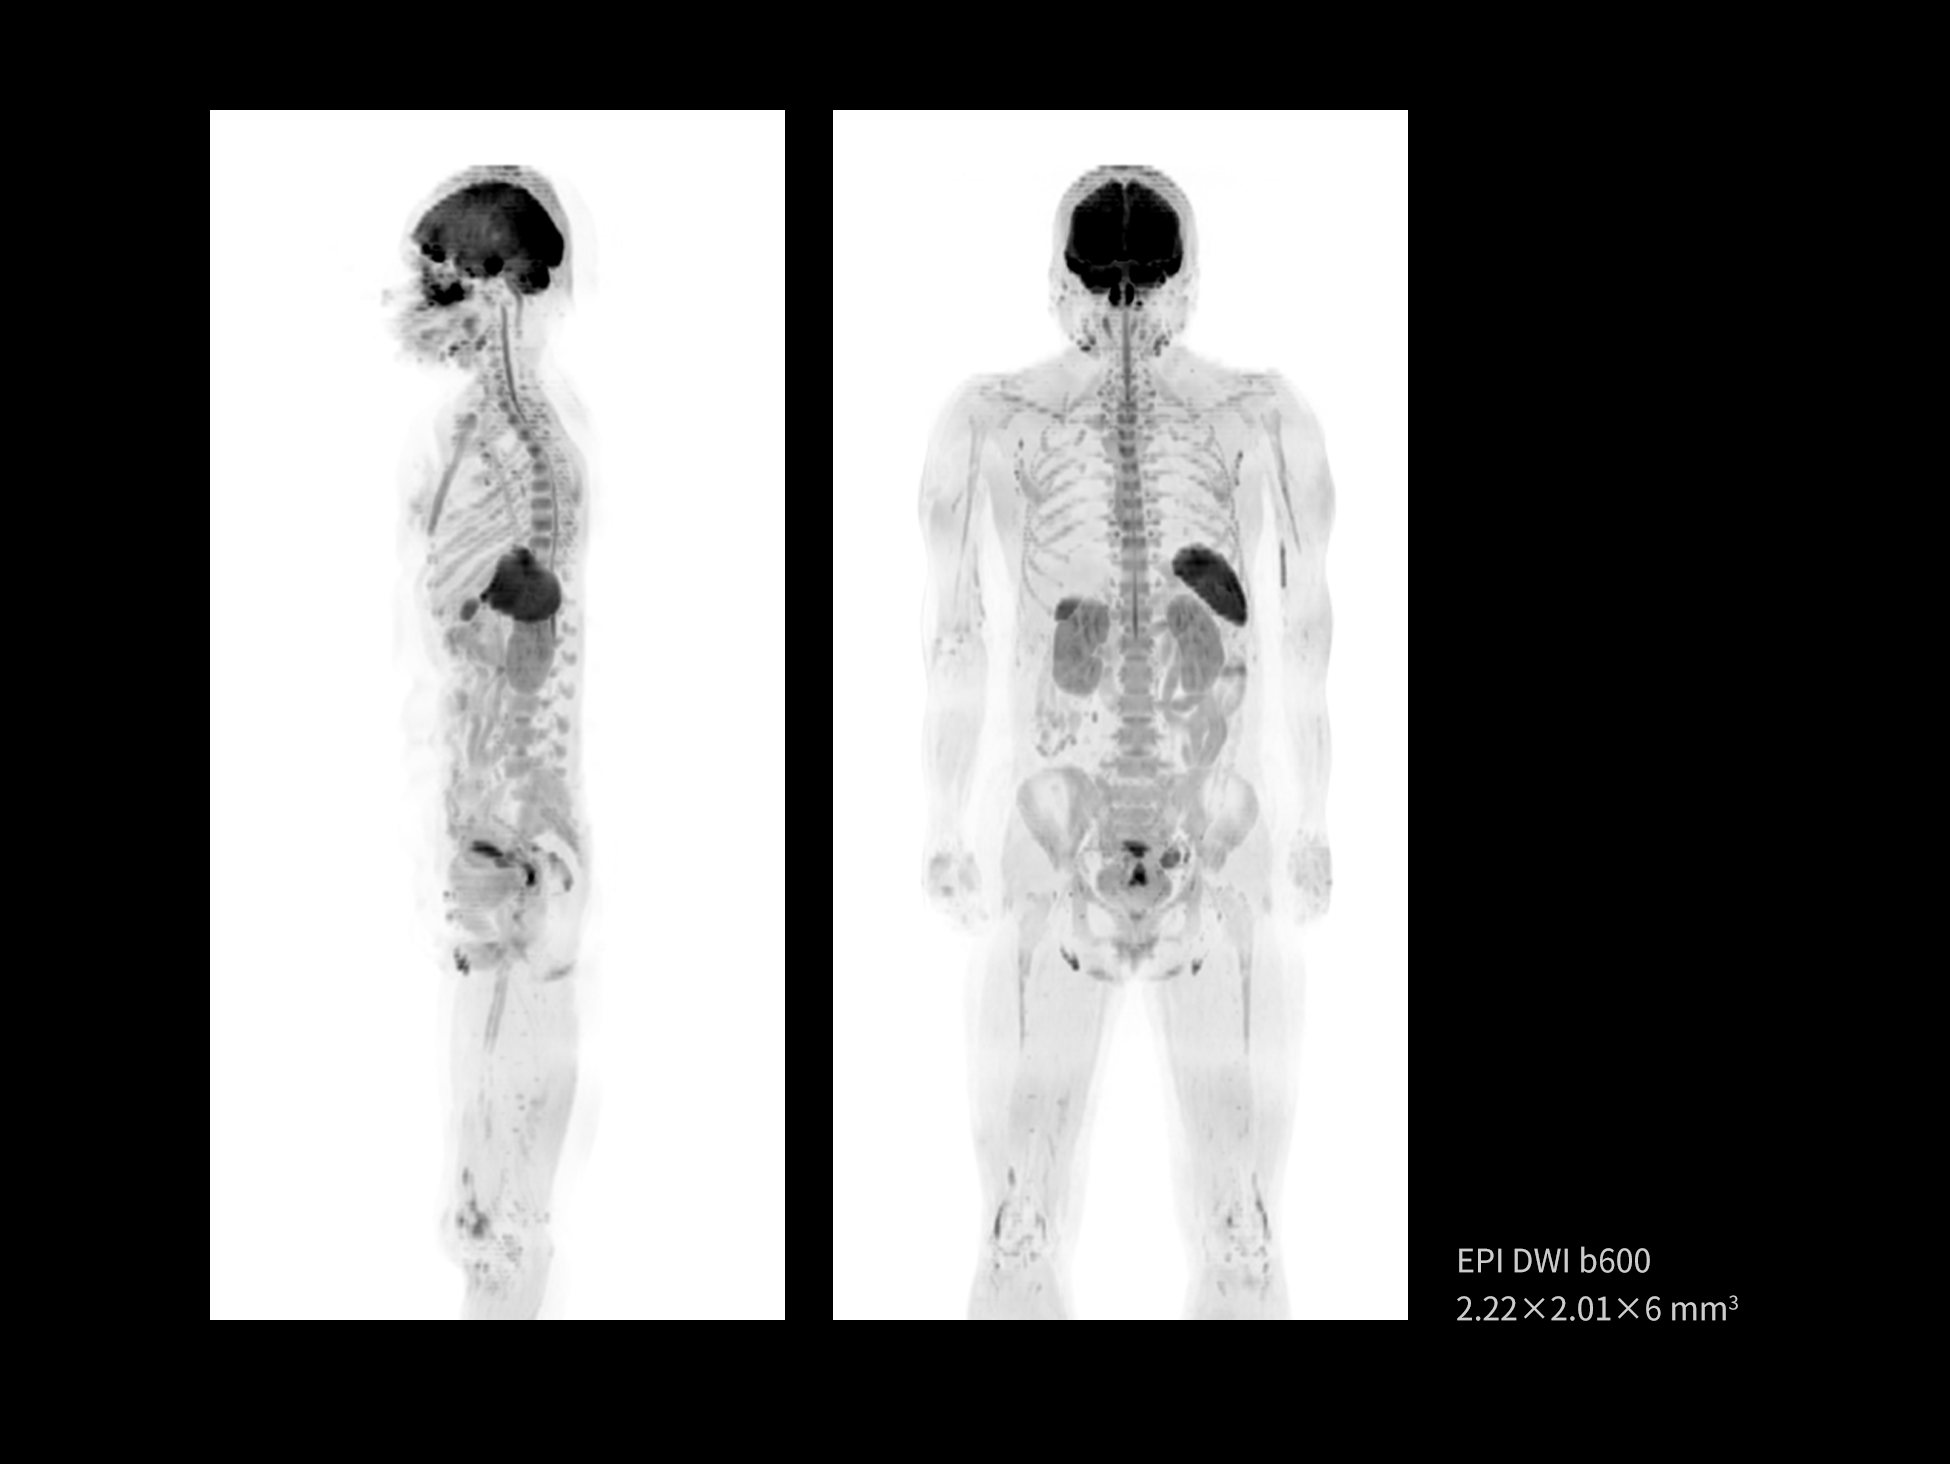

The high homogeneity of the magnetic field supports whole-body DWI, which can assess the diffusion of water molecules throughout body tissues. This technology plays a crucial role in detecting occult lesions and tumor metastasis.

Images courtesy of United Imaging.